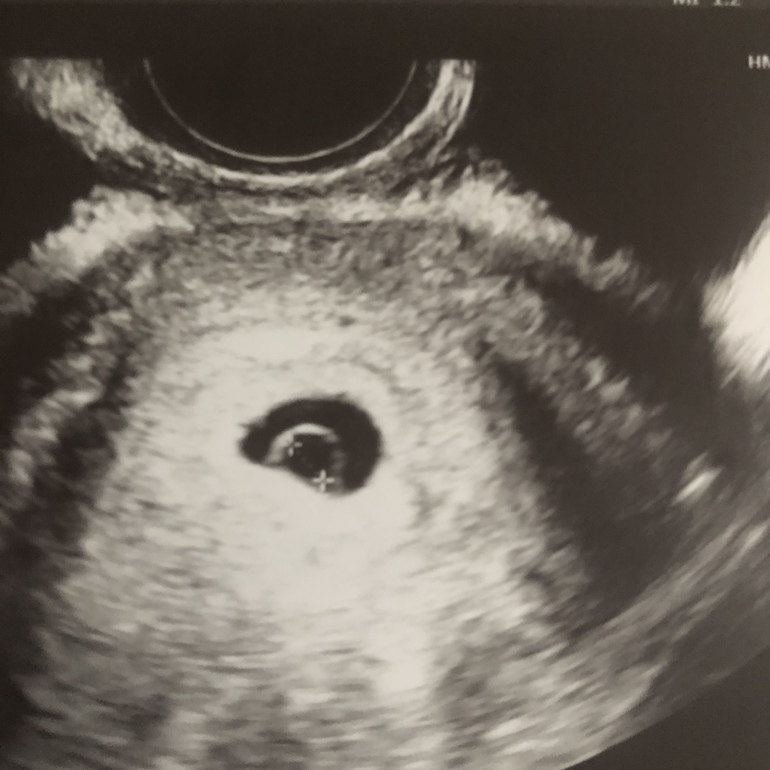

При анэмбрионии пя будет совершенно пустым, как чёрная дыра. У вас на узи явно там что-то есть. На первом снимке очень напоминает жм, а на втором вообще на эмбрион похоже. Посмотрите сами в интернете картинки с узи на вашем сроке. Думаю, надо просто сходить на узи к другому врачу и все у вас найдут!

Кстати не понятно как она про ЖМ ничего не указала,ведь на нижнем фото видно что делают замеры ПЯ,а на верхнем замеры ЖМ(по линиям и плюсикам)А на нижнем фото я б предположила что вобще эмбрион.

Плодное яйцо и желточный мешок , остальное все будет в 7-8 недель)